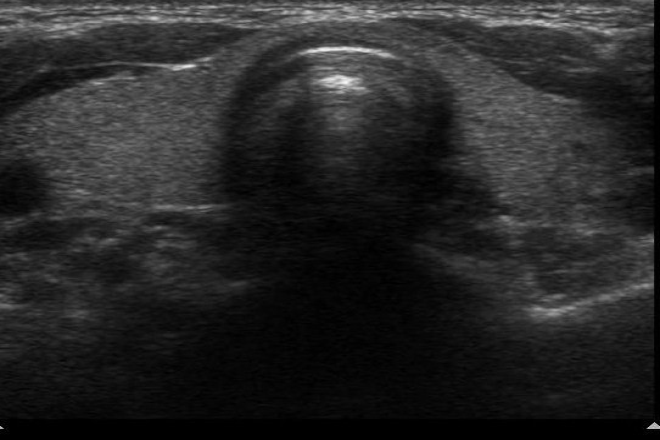

• Identificar nódulos y definir sus características.

Criterios ultrasonográficos de malignidad: Bordes irregulares, hipoecogenicidad, presencia de microcalcificaciones y otros factores aumentan el riesgo de malignidad en nódulos tiroideos.

El Colegio Americano de Radiología desarrolló un sistema de datos y reporte de imágenes tiroideas (TIRADS) para categorizar lesiones tiroideas según su riesgo de malignidad.